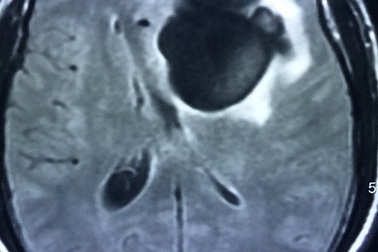

Liệt nửa người, đi khám mới biết sán làm tổ trong nãoĐau đầu, buồn nôn, sốt, tê liệt nửa người, ông S. được người nhà đưa đến bệnh viện. Kết quả kiểm tra cho thấy bệnh nhân có 5 ổ sán rải rác trong não, gây phù não. Đây chính là nguyên nhân dẫn tới các triệu chứng trên.

Sán làm tổ trong não vì 3 món nhiều người Việt thường ănChụp cộng hưởng từ sọ não thấy khối tổn thương ký sinh tại vùng não của bệnh nhân do ấu trùng sán dây lợn.